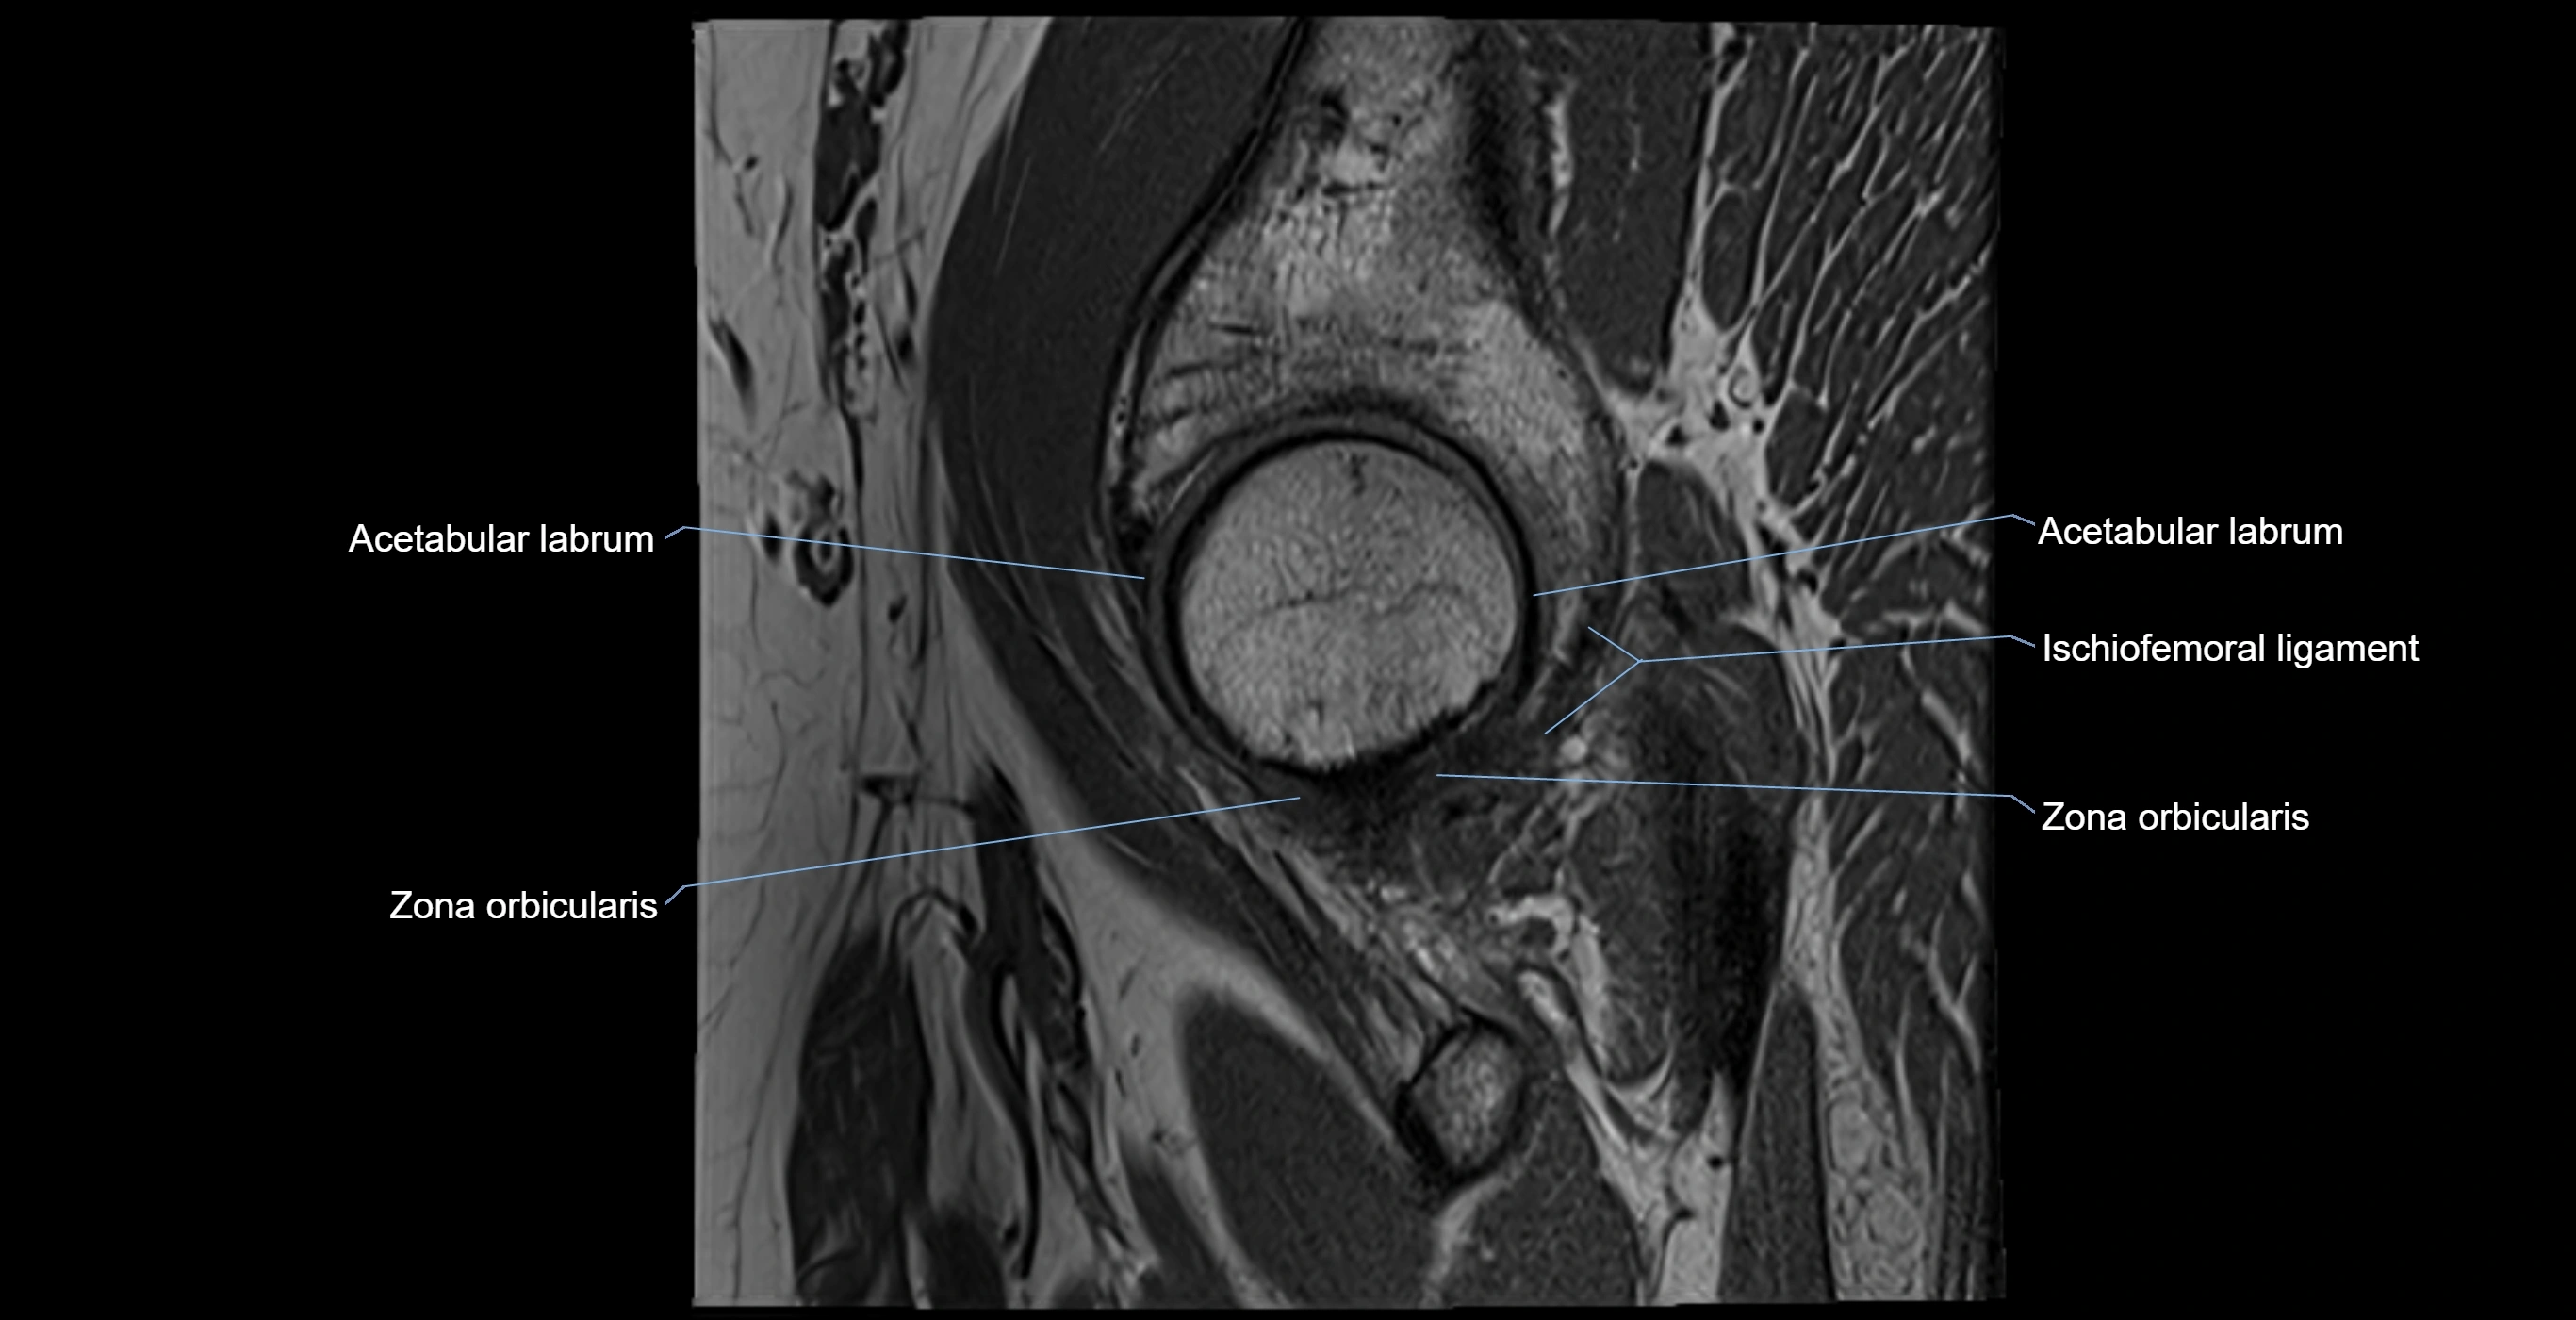

Acetabular labrum

The acetabular labrum is a fibrocartilaginous ring that surrounds the rim of the acetabulum in the hip joint. It deepens the hip socket, increases joint stability, and maintains a suction seal that preserves negative intra-articular pressure. Structurally, the labrum transitions from hyaline cartilage of the acetabulum to dense fibrocartilage at its free edge.

It is triangular in cross-section, with its base attached to the acetabular rim and its apex projecting toward the femoral head. The labrum is most robust superiorly and anteriorly, where load bearing is greatest, and relatively thinner inferiorly.

Structure and Relations

• Superior and anterior labrum: thickest portions, stabilizing against anterior dislocation

• Inferior labrum: blends with the transverse acetabular ligament bridging the acetabular notch

MRI Appearance

T1-weighted images:

• Labrum: low signal intensity (dark)

• Surrounded by intermediate signal joint fluid (bright on arthrogram)

• Tears: linear or focal areas of intermediate-to-high signal interrupting labral continuity

T2-weighted images:

• Joint fluid: bright, making labral tears visible as fluid extending into or around labrum

MRI image

image